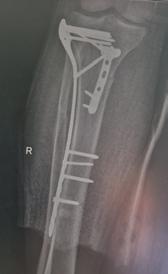

copul. Prezentarea unui caz complex rezolvat în Clinica Ortopedie -Traumatologie din cadrul SCJU Craiova al unui pacient ce a suferit un traumatism postoperator, cu ruptura ligamentului rotulian si complicarea septică a implantului, ce a necesitat revizia în doi timpi și refacerea mecanismului extensor folosind grefă sintetică.

de protezare a genunchiului, cu o evoluție postoperatorie favorabilă, fără complicații. În urma dispensarizării la domiciliu, la 3 săptămâni postoperator, pacientul suferă un traumatism prin cădere de la același nivel, prezentându-se în Serviciul de Urgență tardiv, după aproximativ 10 ore, cu o plagă dehiscentă pe fața anterioară a genunchiului, exteriorizându-se la piele ligamentul rotulian restant, dezinserat de la nivelul polului inferior rotulian. Intraoperator se practica debridare mecano-chirurgicala intensivă, cu îndepărtarea marginilor plăgii, ale țesuturilor necrozate, lavaj intens, abundent și sutura ligamentului rotulian (Fig 1; Fig 2).

Postoperator evoluția este nefavorabilă, cu modificarea markerilor biologici inflamatori (VSH, Fibrinogen, Proteina C-Reactiva ↑), prezența unei hidrartroze restante, pozitive la Staphylococcus aureus meticilino-rezistent (MRSA), ruptura suturii ligamentare, de unde și decizia unei revizii în doi-timpi, conform protocoalelor internaționale și inițializarea antibioticoterapiei țintite cu Linezolid 2mg/ ml, fl II/zi.

În prima etapă s-a îndepărtat proteza primară, s-a practicat debridarea mecano-chirurgicală a țesuturilor neviabile, rezecția ligamentului restant de la nivelul inserției sale tibiale, alezarea canalelor fe-

muro-tibiale, aplicarea perlelor de Stimulan atât in canalele osoase cât și în camera genunchiului, si montarea unui spacer femuro-tibial (Fig 3).

În a doua etapă, după parcurgerea curei antibiotice, se practică revizia cu implantele finale, folosind proteza de revizie de tip balama, cu stem femural și tibial lung, cu protecția oferită de perlele de Stimulan impregnate cu Vancomicină și Linezolid.

Particularitatea cazului o oferă tipul de tehnică chirurgicală folosită în refacerea ligamentului rotulian prin utilizarea unei grefe sintetice, de tipul Marlex mesh. (3) Din experiența noastră folosind multiple tipuri de grefe pentru reconstrucția ligamentului rotulian, rezultatele în timp s-au dovedit ineficiente (evaluarea la 1-3 ani postoperator indică resorbția cu dispariția ligamentului rotulian în întregime în mediu aseptic după folosirea grefei din Banca Națională de Țesut, fiind utilizată atât grefă cu pastilă osoasă calcaeană și tendon Achillean, cât și aparat extensor

întreg – dar osteointegrarea osoasă la nivelul TTA fiind completă), motiv pentru care am decis utilizarea unui substitut alloplastic- meșă (plasă) de polipropilenă 30x30cm care a fost preparată astfel: bucata de material a fost pliat în 8 straturi, având o l=3cm și o L=30 cm, fiind suturată cu fir neresorbabil pe lateralele sale, urmând a fi cimentată in canalul tibial odată cu componenta protetică tibială. După stabilirea indicelui Insall-Salvati corect, s-a folosit o langetă musculară din dreptul femural după tehnica Ducroquet care a acoperit noul ligament sintetic, oferind protecție si bază nutritivă și a fost stabilizat cu ajutorul a 2 ancore cu fire nerserobabile (Fig 4+5+6). Postoperator pacientul este imobilizat în aparat gipsat femuro-gambier pentru 6 săptămâni, mărind treptat gradul de flexie.